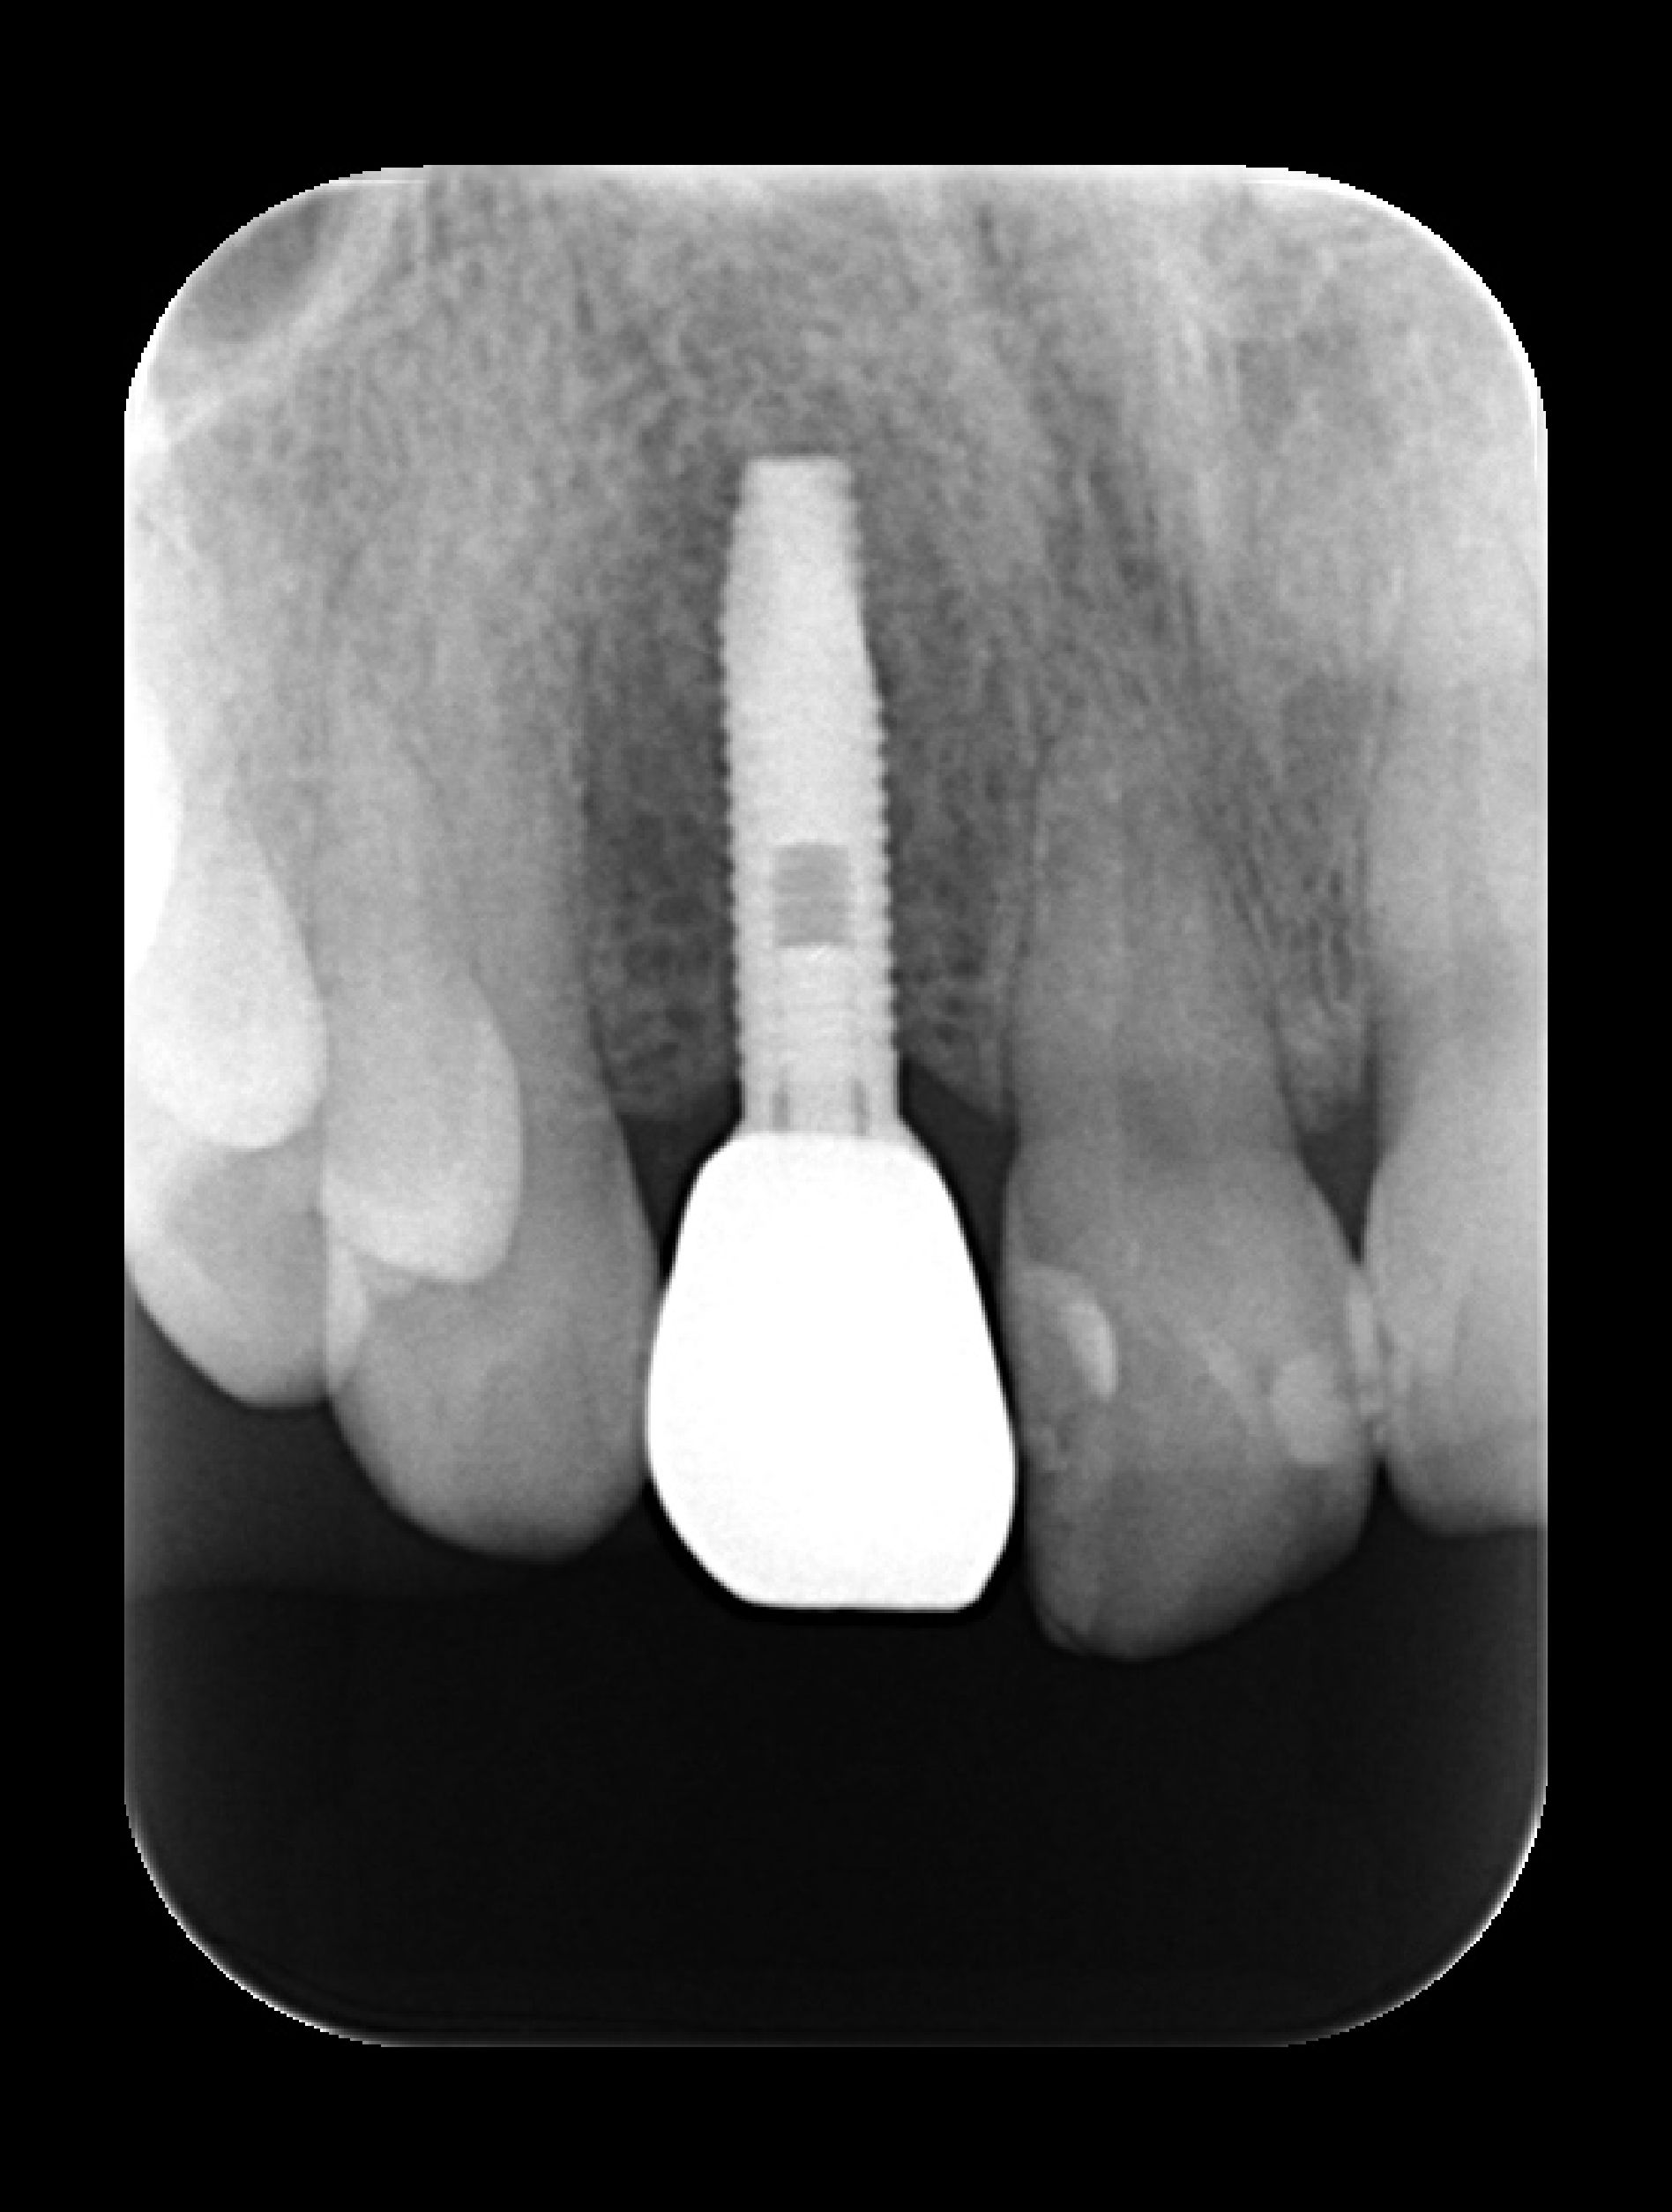

失敗例2 インプラントの部分に金具が見えている

これは骨が足りない上に、歯茎も足りないため金具が露出してしまっている状態です。

「これでは歯を見せて笑えない」と悩んで当院にセカンドオピニオンでいらっしゃいました。インプラントは骨を作るときに、歯茎が足りない場合は歯肉移植も同時に行うことがありますが、今回はそのどちらも行われていなかったため、このような状態になっておりました。